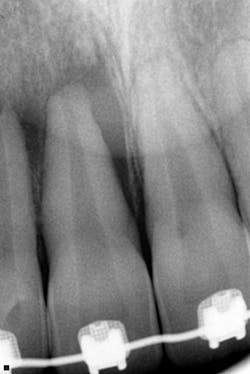

Suspecting an abscessed tooth, she immediately took a periapical radiograph. Note the extensive bone loss apically and along the mesial portion of the root of tooth no. 8 (almost resembling a lateral periodontal cyst) in Figure 2. In addition, note the very large (gigantic!) pulp resembling taurodontism, as well as an immature apex on all the anterior teeth.